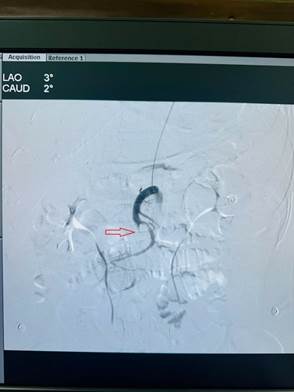

: Huyết khối gây tắc phần lớn động mạch mạc treo tràng trên và các nhánh

Hình 1: Huyết khối gây tắc phần lớn động mạch mạc treo tràng trên và các nhánh

Ngay lập tức, cuộc hội chẩn liên khoa giữa khoa Ngoại Tổng hợp, Hồi sức tích cực – chống độc, Chẩn đoán hình ảnh và đơn vị Tim mạch can thiệp được diễn ra, các bác sĩ xác định tình trạng thiếu máu ruột của bệnh nhân chưa dẫn đến hoại tử ruột (chưa có phản ứng thành bụng, dấu hiệu nhiễm trùng nhiễm độc chưa rầm rộ, chưa có dấu hiệu hoại tử ruột trên phim cắt lớp vi tính) và đi đến thống nhất chỉ định can thiệp lấy huyết khối động mạch mạc treo dưới số hóa xóa nền. Bệnh nhân được chuyển vào phòng tim mạch can thiệp, các bác sĩ tiến hành chụp và can thiệp hút ra rất nhiều huyết khối, tái thông động mạch mạc treo tràng trên.